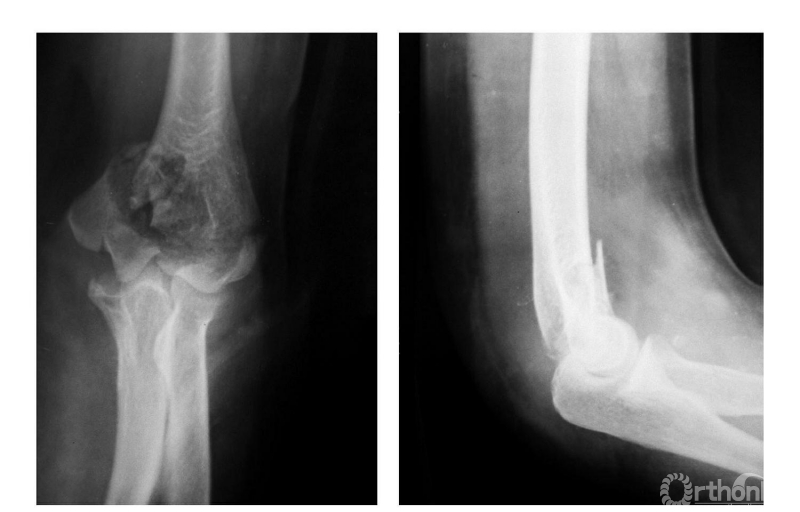

例3:肱骨髁间碎折仅有轻度尺偏(Ⅳ型)(图3)。

图3